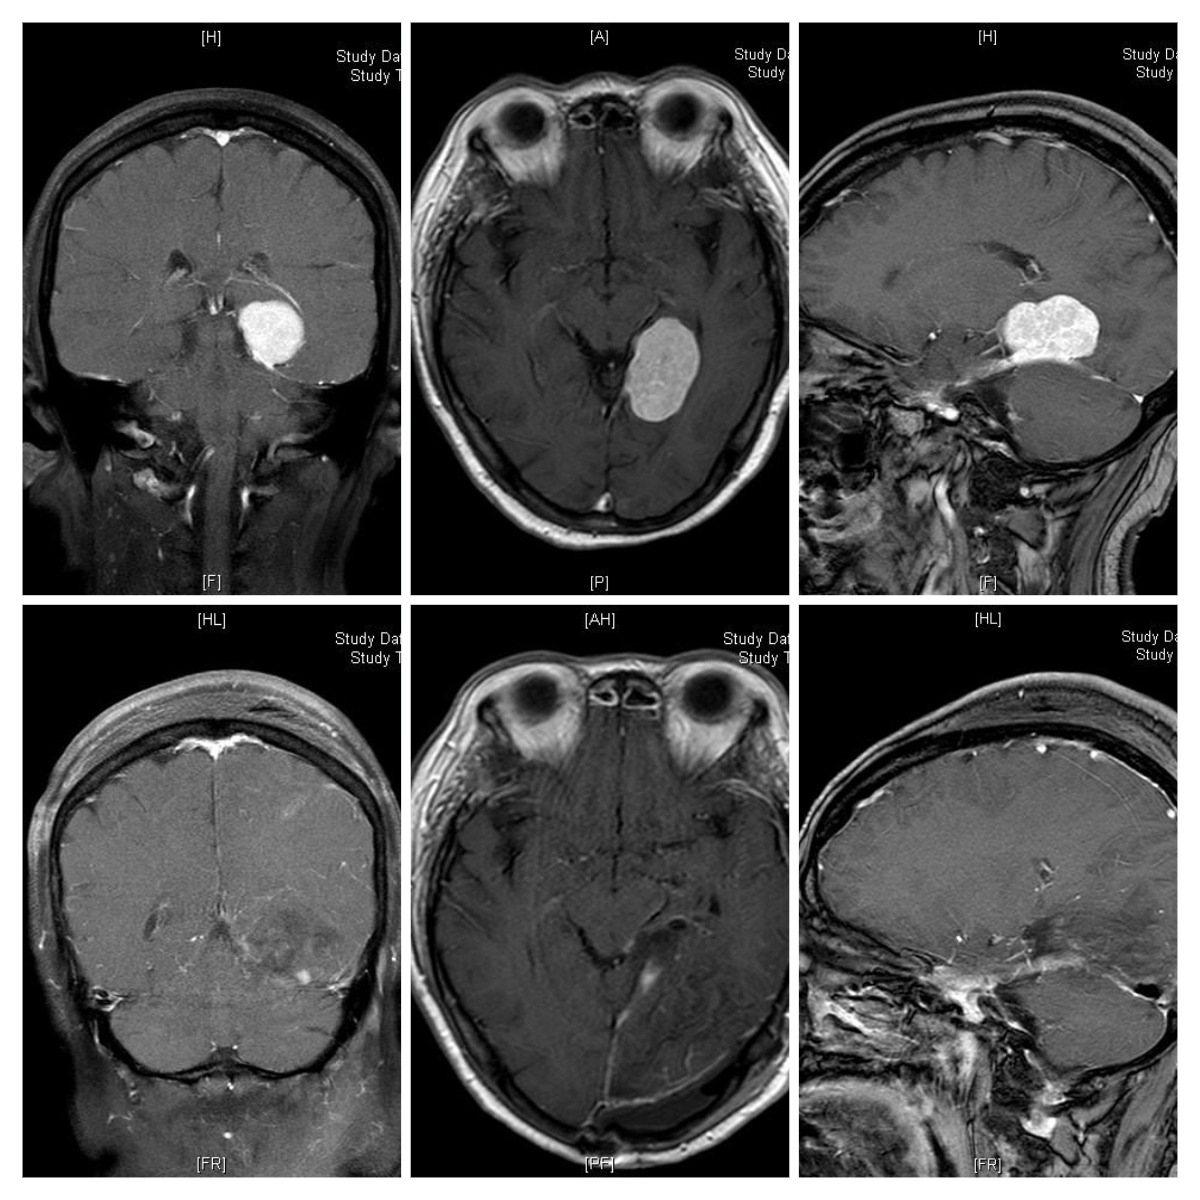

67岁的吴阿婆近半个月来突然感觉持续头疼头晕、视力模糊,经头颅CT、颅脑MRI平扫+增强检查发现,她左侧颅底深部、小脑幕缘竟长了一个40X50X40mm的巨大肿瘤,邻脑组织严重受压,视觉中枢受到推挤,随时有突发脑疝的危险,必须马上手术。

术前(上三张)术后(下三张)增强磁共振对比,白色肿瘤物完全切除干净